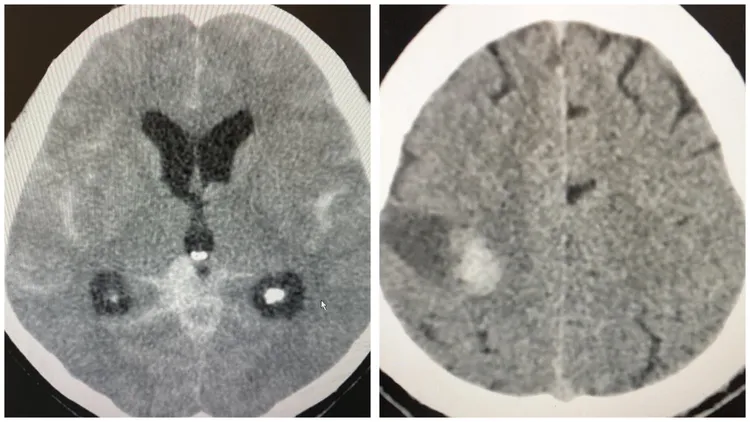

林婷今天一早投完票有感而發,在《林婷一下吧 icu護理師》粉專表示,她今晚上夜班,希望能平平安安的上班、準準時時下班!她表示有一次開票之夜,遇到一名阿嬤情緒太激動腦血管破裂,送來已經嘴角歪,一邊說話含糊不清,仍在喊「凍蒜」、「凍~~」,一量血壓198/98,動脈瘤破裂出血,索性從鬼門關前救回一命。

她表示緊急幫阿嬤做了腦部動脈瘤栓塞手術,但腦部出血造成腦水腫,後來必須開腦再放個引流管,減輕腦部壓力,她呼籲大家不要因選舉太過激情造成血壓波動,真的得不償失呀!她寫道:「在icu我們碰過各種因為活動及情緒激動引起的血壓波動,造成腦部動脈瘤破裂,例如:老公跟老婆吵架生氣、大媽打麻將胡了一把過於激動,中年男子在廁所上大號太用力、外遇男子偷情小三跑走,都是血壓突然升高的誘因,血壓超過血管壁所能承受的壓力,血管就可能會破裂出血造成中風。」